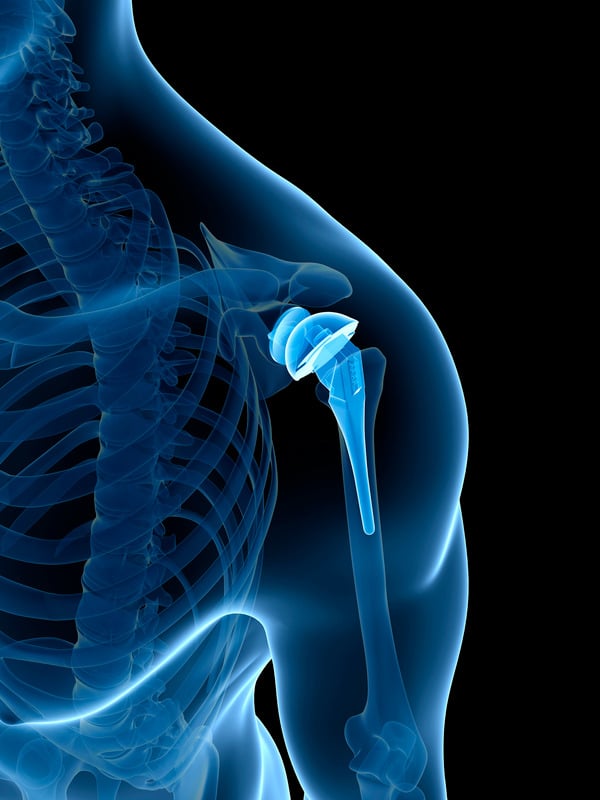

• Αρθροπλαστική Ώμου: Η αρθροπλαστική ώμου περιλαμβάνει την αντικατάσταση της κατεστραμμένης άρθρωσης του ώμου με ένα τεχνητό εμφύτευμα.

Χρησιμοποιείται κυρίως για τη θεραπεία σοβαρών περιπτώσεων οστεοαρθρίτιδας και ρήξης του στροφικού πετάλου.